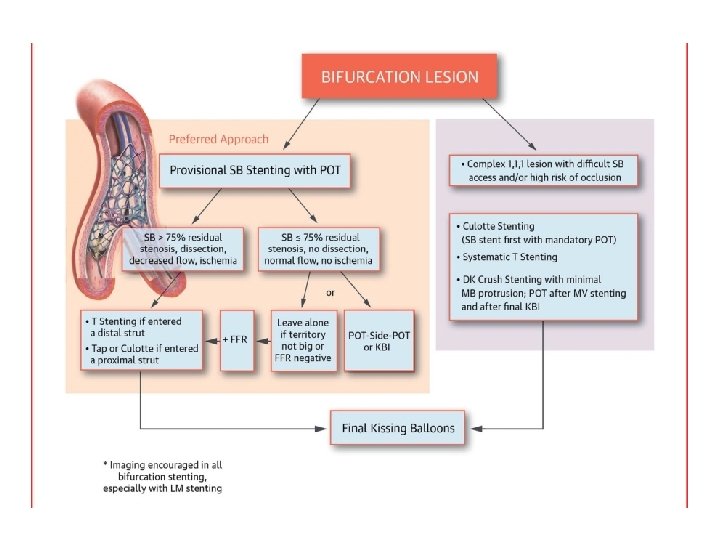

Stenting techniques 1)Provisional • Mainvessel stenting ± side branchangioplasty (Provisional) Tstenting, • TAP, • REVERSEINTERNAL CRUSH • REVERSECULOTTE. 2) elective • Culotte-stenting • Crush technique (reversecrush) T TECHNIQUE AND TAP • V STENTING • Y STENTING(SKS technique)

Provisional stenting strategy 1. Both branches are wired starting with the most difficult one 2. MB is stented (stent sized according to MB distal reference) and SB wire is jailed 3. The stent is post-dilated using the Proximal Optimization Technique (POT) to maximize stent apposition 4. Stent is now well apposed proximally, while the SB is partially covered by scaffolding 5. MB wire is pulled back and reinserted through the most distal strut of the SB opening scaffold 6. Jailed wire is removed and re-inserted in the distal MB (with a formed loop at the distal end) 7. The Kissing Balloon inflation is done to optimize side branch flow and access 8. Final result (if suboptimal, can then place additional stents)